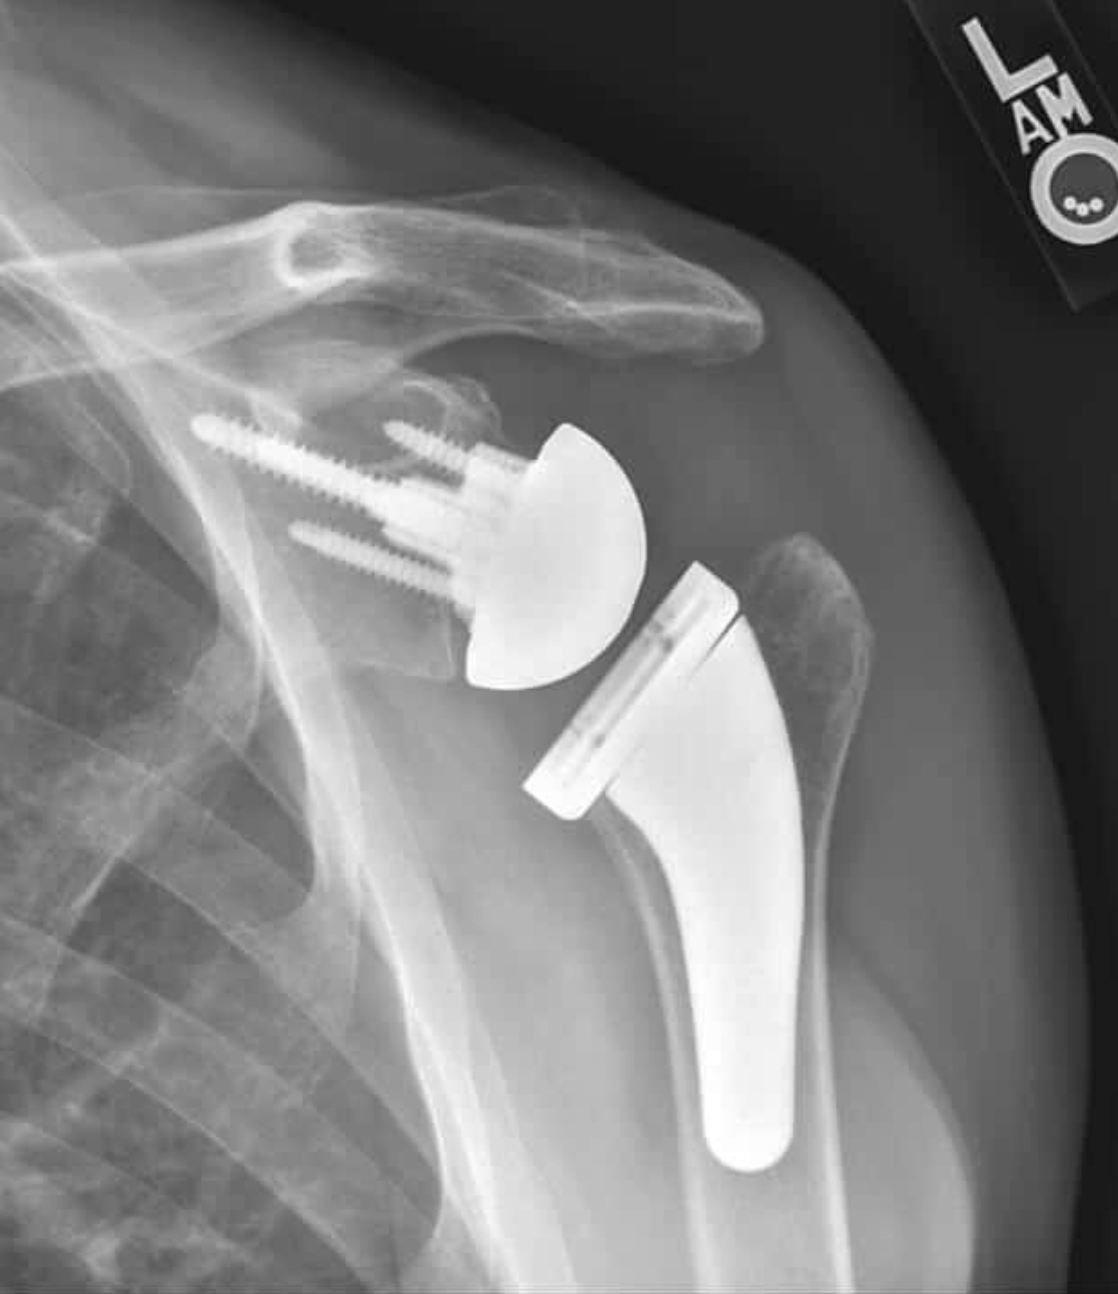

Reverse Total Shoulder Arthroplasty (RTSA):

- In RTSA, the normal ball-and-socket structure is switched: the ball is placed on the shoulder blade, and the socket is placed on the upper arm bone.[3][4][5]

- RTSA is designed for people with a torn or irreparable rotator cuff, severe shoulder arthritis, or major bone loss in the socket.

- It is often used for older adults, those with complex fractures, or those at risk for future rotator cuff problems.[1][2][6][10][7][11][12]

- RTSA does not rely on the rotator cuff for movement. Instead, the deltoid muscle (on the outside of your shoulder) helps lift your arm.[1][2][13][10][3][4][11]

- RTSA can provide reliable pain relief and improved ability to raise your arm overhead, especially if you had trouble lifting your arm before surgery.[8][14]

- Some patients may have slightly less rotation compared to ATSA, and RTSA may have a higher risk of certain complications if the rotator cuff is healthy.[13][6][14][9]

X-ray image showing a shoulder with a reverse total shoulder arthroplasty

X-ray image of a right shoulder with reverse shoulder arthroplasty